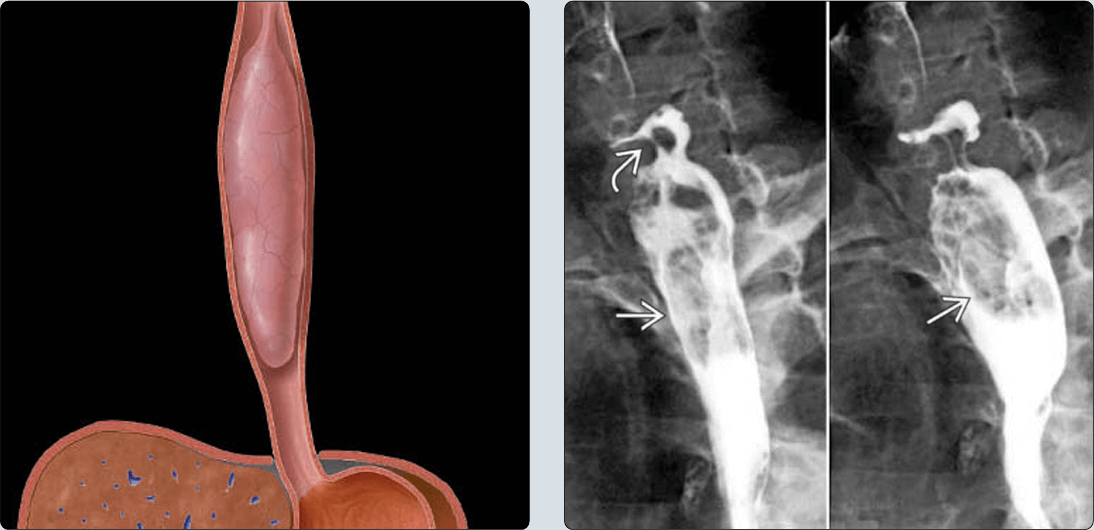

* Chụp TQ cản quang

– Thực hiện trước mổ hoặc khi ống soi không thể đi qua đoạn hẹp.

– Xác định vị trí, chiều dài, giới hạn trên và dưới của tổn thương, đánh giá lưu thông dạ dày.

– Thể thâm nhiễm: hình ảnh hẹp lòng thực quản, hẹp không đều, lệch trục, ngoằn ngoèo, khúc khuỷu.

– Thể u sùi: hình khuyết bờ không đều, nụ sùi lớn có thể làm tắc lòng thực quản.

– Thể loét sùi: khối u bị hoại tử tạo nên những ổ đọng thuốc giữa các hình khuyết. Biểu hiện bằng 1 ổ loét bao quanh bởi một gờ sáng gọi là loét thấu kính.

– Chẩn đoán X-quang:

+ Khối hình trứng giới hạn rõ bởi thuốc cản quang.

+ Ranh giới tạo góc tù với thành thực quản.